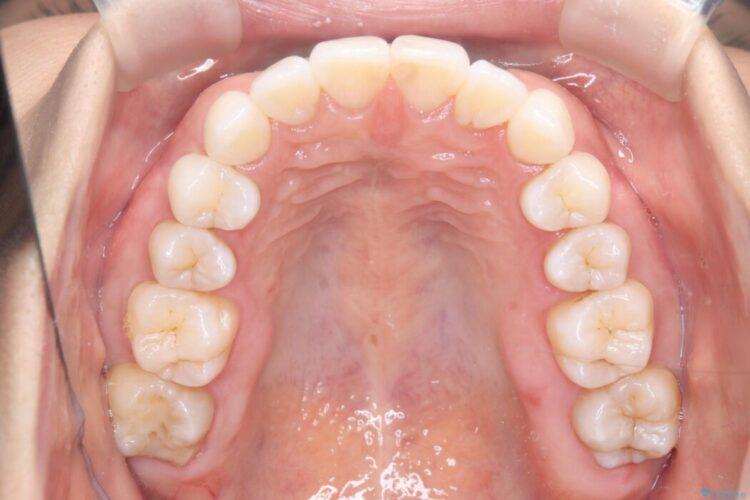

治療完了後、前歯のガタつきはきれいに整い、上下の奥歯も理想的な位置で噛み合うようになりました。非抜歯での治療により、ご自身の歯をすべて残したまま、機能的で美しい歯並びを実現することができました。